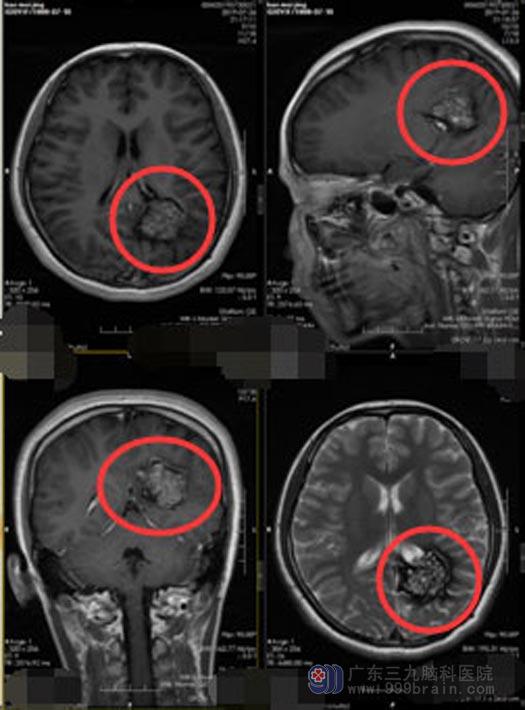

考虑是良性肿瘤可能性大,神经外五科医师团队经过详细讨论,为小静制定了针对性的手术方案,决定实施球囊辅助精准定位,左侧侧脑室后角巨大占位切除术。虽然占位比较大,术中仍可以利用微创技术,显微镜下将肿瘤分块全部切除,周围重要的神经及血管保护完好,手术完成顺利。术后小静恢复良好,无任何不良并发症。

▲手术前